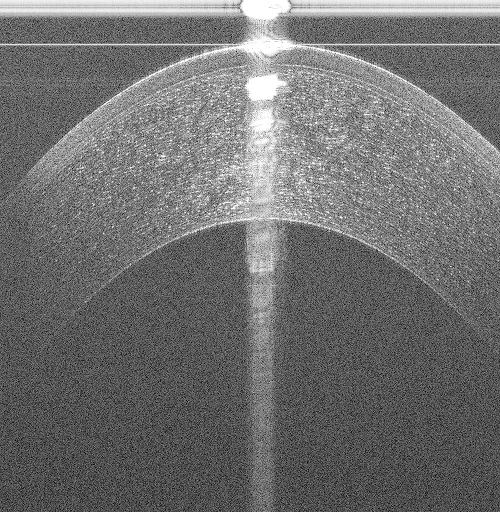

While many non-proprietary image analysis-based corneal interface segmentation approaches exist [6, 7, 8, 9, 10] in literature, they do not generalize to volumes acquired from different OCT scanners. These approaches are ad-hoc with key parameters being chosen manually; for example in Fig. 1, recent approaches [6, 7, 10], developed for images (B-scans) acquired by a Spectral Domain OCT (SD-OCT) scanner scanning a 66mm area, failed while segmenting the Epithelium (shallowest layer) in 33mm volumes acquired by a Ultra High Resolution OCT (UHR-OCT) scanner. Assumptions on the central artifact location [6, 7, 8, 9, 10] break down when they are located in different regions of the image (see Fig. 1(c)). As shown in Figs. 1(a) to 1(c), a segmentation approach must perform reliably across datasets acquired with different scan settings from different scanners, even in the presence of strong vertical and horizontal specular artifacts.

(a)

(b)

(c)

(d)

(e)